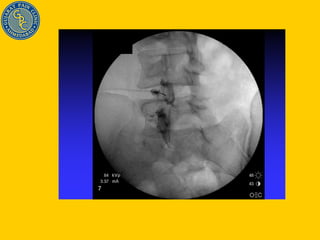

Injection Technique done with C-arm fluoroscopic device Steroid Reverses effect of inflammatory mediators Stops inflammation cascade Helps in healing annular tear Stabilizes cell membrane Delays pain impulse conduction Gives pan/ inflammation free time for disc herniation to settle down by natural process (Natural history of disc disease)

Injection Technique

L4 nerve Root